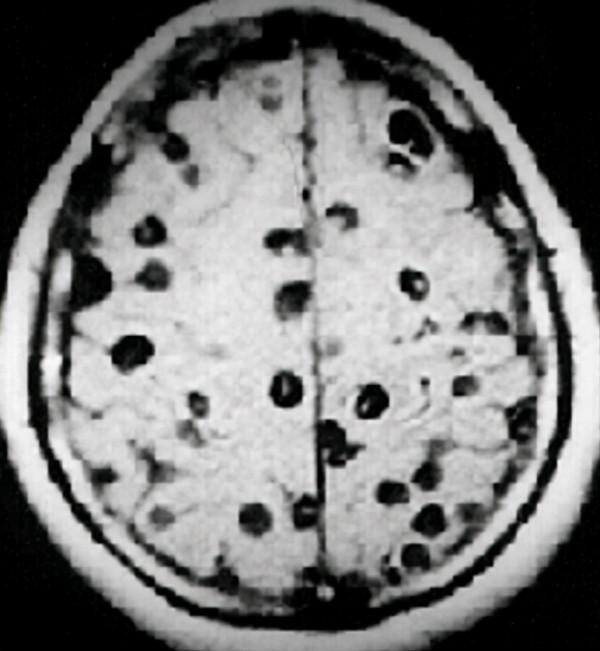

這種方法看似神奇,卻十分的兇險。首先,絛蟲是寄生蟲的一種型別,雌雄同體的它們,完全可以透過自身的繁殖能力,大量繁衍子孫後代。吞下一隻絛蟲,等於吞下一個龐大的絛蟲家族。

除此之外,絛蟲在人體內隨時能侵入面板和大腦,使人患上嚴重的面板疾病和精神病。但即便如此,減肥減到瘋魔的英國女性,在瞭解到絛蟲的危害後,依然以身犯險地嘗試。